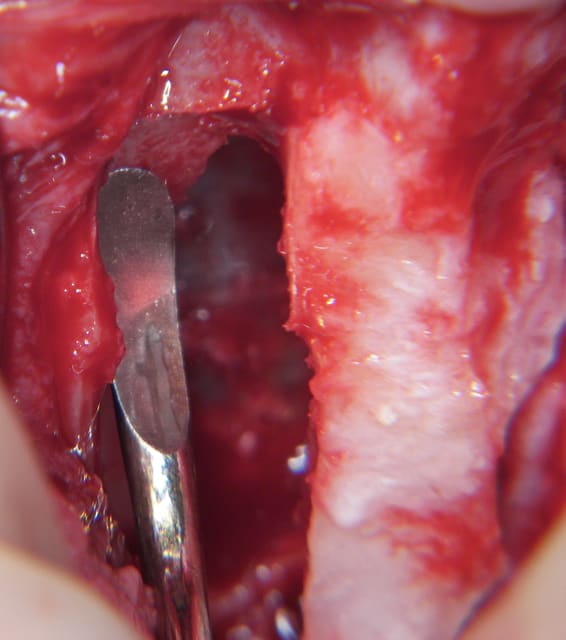

je viens de faire un sinus lift ce matin;

- 3 à 4 mm de hauteur sous sinusienne

- des cloisons de refend partout

- comblement avec du Vital Os

- un implant Axiom D4 L 10

comme je n'avais pas le temps de faire des photos la dernière fois et que j'en étais frustré, je me suis un peu lâcher aujourd'hui...

les premières photos, c'était ouverture par voie latérale